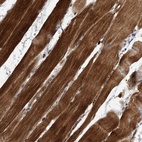

Immunohistochemical staining of human skeletal muscle shows strong cytoplasmic positivity in myocytes.